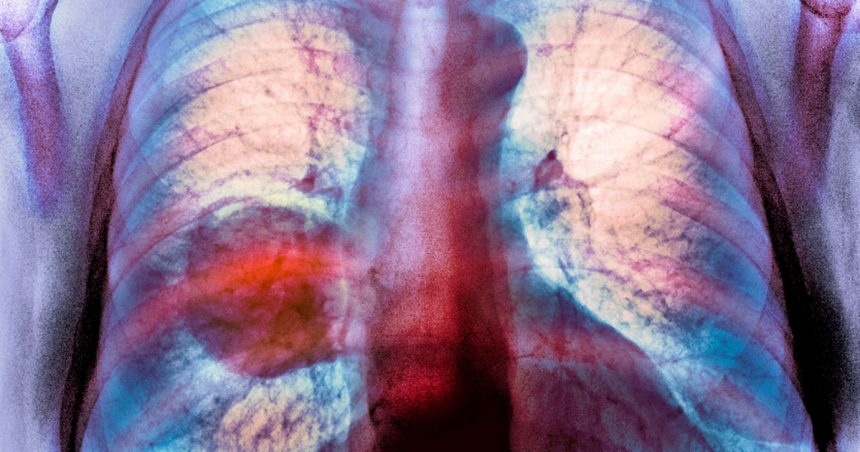

Proporția persoanelor diagnosticate cu cancer pulmonar care nu au fumat niciodată este în continuă creștere, iar poluarea aerului este un „factor important”, conform unei analize efectuate de Agenția Internațională pentru Cercetare a Cancerului (IARC), parte a Organizației Mondiale a Sănătății. Această formă de cancer este acum estimată a fi a cincea cauză de deces prin cancer la nivel mondial.

Cancerul pulmonar la persoanele care nu fumează apare aproape exclusiv sub forma adenocarcinomului, care a devenit cel mai dominant subtip al bolii atât la bărbați, cât și la femei. În 2022, aproximativ 200.000 de cazuri de adenocarcinom au fost asociate cu expunerea la poluarea aerului. Cele mai mari proporții de adenocarcinom atribuite poluării aerului au fost identificate în Asia de Est, în special în China.

Dr. Freddie Bray, autorul principal al studiului, a subliniat necesitatea unei monitorizări urgente a riscurilor în schimbare legate de cancerul pulmonar. El a menționat că, pe măsură ce prevalența fumatului scade, cum se observă în Marea Britanie și SUA, proporția de cancere pulmonare diagnosticate în rândul celor care nu au fumat niciodată tinde să crească. Aceasta ridică întrebări cu privire la factorii cauzali, cum ar fi poluarea aerului, care ar putea contribui la această tendință.

Adenocarcinomul reprezintă până la 70% din cazurile de cancer pulmonar în rândul persoanelor care nu fumează niciodată, iar tendințele actuale sugerează o reducere a diferențelor de incidență a cancerului pulmonar între bărbați și femei. În 2022, aproximativ 900.000 de femei au fost diagnosticate cu această boală, ceea ce reflectă o schimbare semnificativă în modelele de incidență ale cancerului pulmonar la nivel mondial.

Creșterea cazurilor de cancer pulmonar la nefumători

Studiile recente sugerează că incidența cancerului pulmonar este în creștere în rândul persoanelor care nu fumează niciodată. Deși nu se cunoaște exact proporția cazurilor globale de cancer pulmonar în rândul acestor indivizi, dovezile disponibile indică o tendință alarmantă.

Un raport al IARC subliniază că poluarea aerului joacă un rol semnificativ în această creștere, contribuind în special la apariția adenocarcinomului. Conform studiului, adenocarcinomul reprezintă între 53% și 70% din cazurile de cancer pulmonar la persoanele care nu au fumat niciodată.

Oamenii de știință continuă să investigheze cauzele cancerului pulmonar dincolo de fumat, având în vedere că schimbările în tiparele de fumat și expunerea la poluarea aerului sunt factori determinanți pentru modificarea profilului de risc al incidenței acestui tip de cancer.

Aceste descoperiri oferă indicii importante despre măsurile de prevenire a cancerului pulmonar la nivel mondial, evidențiind necesitatea de a aborda problemele legate de poluarea aerului.